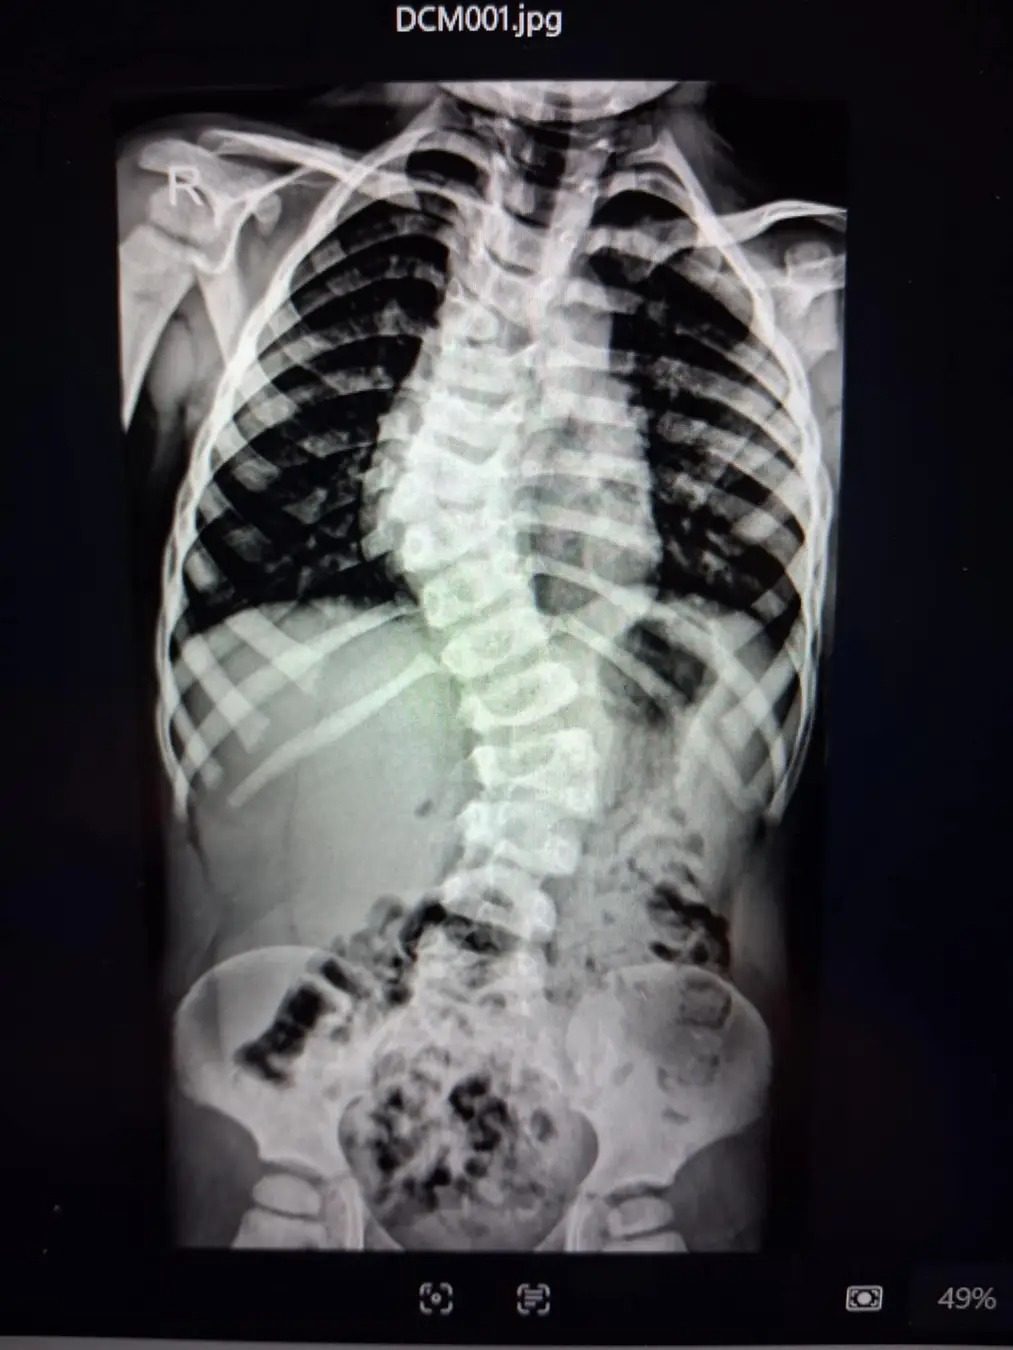

W wieku 7 miesięcy Jasiu miał tę operację, a teraz cały czas jest pod kontrolą Uniwersyteckiego Centrum Klinicznego w Gdańsku. Od maja 2023 roku Jasiu zaczął nosić aparaty słuchowe oraz zaczął uczęszczać na terapię słuchu, gdyż badania ABR potencjałów słuchowych wykazały obustronny niedosłuch na poziomie umiarkowanym. Gdy Jasiu skończył roczek i zaczął chodzić, okazało się, że ma wadę kręgosłupa (ma trzy półkręgi w kręgosłupie), co się wiąże z tym, że jego kręgosłup przy każdym skoku wzrostowym wykrzywia się i powoduje coraz większą skoliozę. Regularna rehabilitacja, to przygotowanie go na operację i jedyna szansa powstrzymania postępowania skrzywienia kręgosłupa. Od urodzenia Jasiu jest rehabilitowany metodą NDT Bobath i metodą Vojty z powodu obniżonego napięcia mięśniowego oraz asymetrii ułożeniowej. Jest także pod stałą opieką wielospecjalistyczną: kardiologiczną, neurologiczną, nefrologiczną, audiologiczną, ortopedyczną, laryngologiczną, psychologiczną, fizjoterapeutyczną oraz surdopedagogiczną. Kontrolujemy Jasia także w poradni genetycznej, aby dokładnie zlokalizować źródło jego problemów.